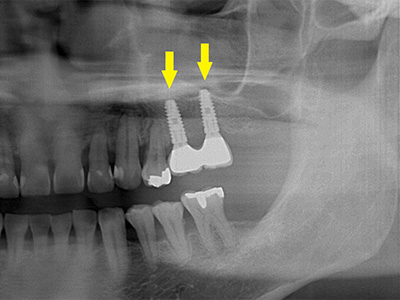

骨移植手術数か月後に、移植した骨片が周囲骨に生着したので、インプラントを埋入した時のレントゲン写真です。

十分な骨量が確保されていましたので、下方を走行する神経を損傷することなく埋入が可能になりました。 -